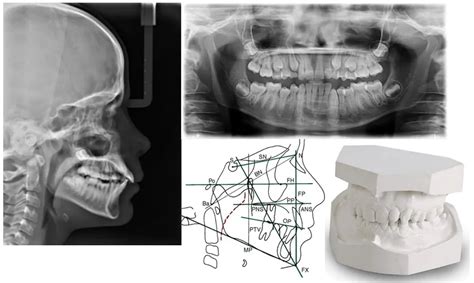

5. Radiografías: Ortopantomografía, periapical y TLRx

Antes de llevar a cabo cualquier otro tratamiento preortodoncia también podrá ser necesario realizar una serie de radiografías con la finalidad de conocer la posición de los dientes y detectar caries u otras patologías. Dentro de las radiografías encontramos:

- Ortopantomografía (OPG): Esta es una radiografía general de toda la boca que se realiza en la primera consulta. De las tres, esta es la única que se realiza a todos los pacientes sin excepción, ya que es vital para detectar problemas que pueden afectar al uso de ortodoncia.

- Radiografía periapical: Las radiografías periapicales son aquellas que se realizan solamente de una o dos piezas dentales. Básicamente sirven para detectar caries.

- TLRx o Teleradiografía Lateral de Cráneo: Es aquella que se realiza con la finalidad de estudiar el crecimiento facial de las personas sometidas a un tratamiento de ortodoncia. Este tipo de radiografía es más frecuente cuando el tratamiento de ortodoncia se realiza con brackets. En otras palabras, podemos decir que esta es una radiografía del perfil del paciente. Sirve para estudiar las proporciones del cráneo y determinar si son las adecuadas.

- Radiografías: Se realizan radiografías para obtener una imagen general de los dientes y los huesos maxilares.

- Toma de impresiones: Se toman impresiones de los dientes para crear modelos de estudio. Esto puede hacerse de manera tradicional o digital.